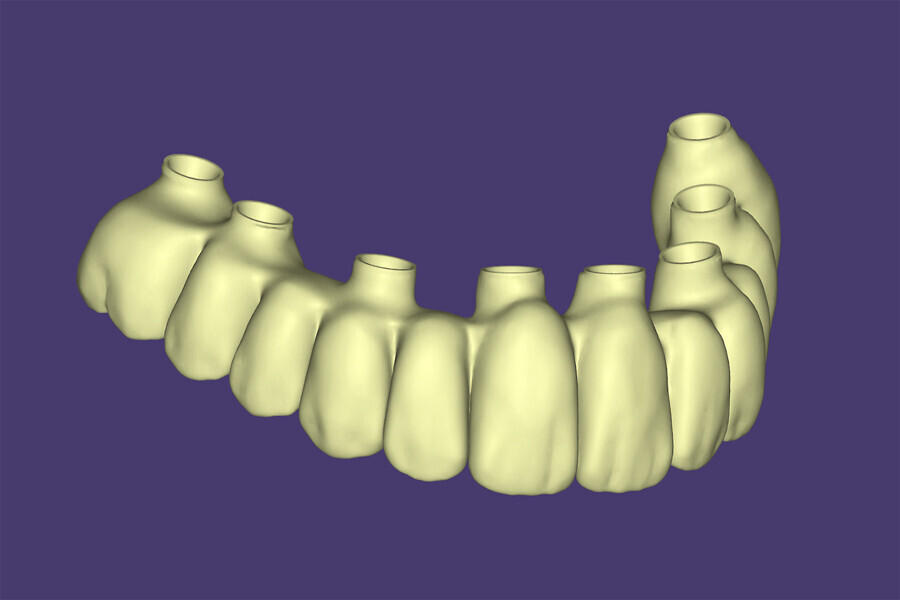

The data collected was sent through a scanning software portal (Medit Scan for Clinics) to the dental laboratory with requested changes for correction of the desired smile design. Utilising advanced planning features in the design software (exocad), the midline and tooth size changes were corrected. 3D-printed maxillary and mandibular PMMA restorations were used for try-in using the direct-to-MUA screws (Vortex LA VIS; Fig. 16a). Fit, phonetics, aesthetics and occlusion were evaluated and confirmed using digital articulation (OccluSense; Fig. 16b). The patient was extremely satisfied with the printed try-ins. Since no adjustments were required, the patient was allowed to leave with the printed try-ins as new provisional restorations made from extra-strong resin. The new provisional restorations were worn for ten days to confirm form and function. The final shade was chosen, and metal-free monolithic zirconia restorations were then fabricated by the laboratory.

The final restorations were passively and accurately seated ten days later uneventfully using Vortex LA VIS screws. Confirmation records were taken with photographs, radiographs and digital articulation to recheck fit, function, phonetics and occlusion (Fig. 17a). The patient was extremely satisfied with his final restorations, describing the process as life-changing and surprisingly fast in comparison with what he had heard about full-mouth implant therapy. He was especially pleased with the speed at which the final process was able to be completed (Figs. 17b & c).

In this case, three methods were utilised to capture data to provide a basis of comparison. The first, photogrammetry, has been acknowledged as the gold standard for implant position accuracy. The second, Grammetry, utilised the new OptiSplint analogue luting protocols. The third, digital capture, utilised the Grammetry OptiSplint, in which the intra-oral scanner and extra-oral desktop captures were analysed and compared. The extra-oral desktop capture of the Grammetry OptiSplint was almost identical to the photogrammetry capture when both data sets were superimposed. The extra-oral desktop capture of the Grammetry splint yielded marginally better results than the intra-oral scan captured extra-orally. Although the results may be slightly less accurate due to the human error associated with intra-oral scanners, they were more than acceptable, as CAD/CAM unit tolerances prevent milling beyond the results obtained. An added benefit of using the Grammetry process is the possibility of producing a physical model, allowing for an analogue try-in for producing both printed try-in and final milled restorations.